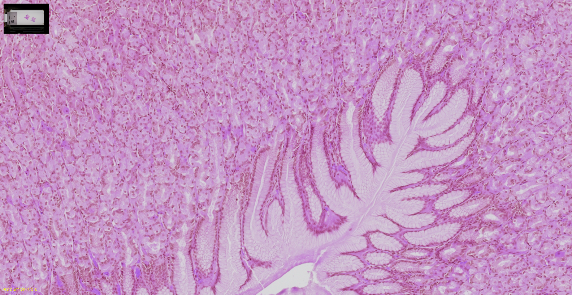

清晰捕捉各种组织和染色的细节

胃组织,H&E(苏木素和伊红)染色